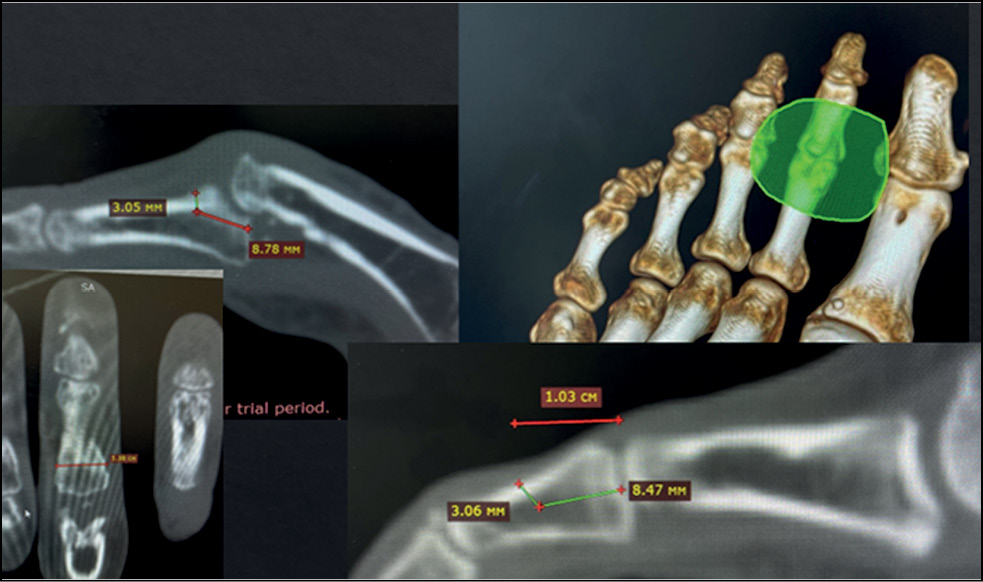

In the preoperative period, multislice spiral CT was used to determine the spatial visualization of the affected bony anatomical structures of the fingers and the features of malunion fractures of the palmar edge of the base of the middle phalanx of the patient’s triphalangeal fingers. The results of multislice spiral CT are stored in DICOM format and transferred to Dolphin Imaging to form DICOM files. A solid three-dimensional (3D) model of the STL phalanx of the patient’s damaged finger and the necessary bone autograft is formed, showing the affected bone anatomical structures and anomalies of the damaged phalanx made of biocompatible and non-toxic polymer material. Acrylonitrile butadiene styrene, polyethylene terephthalate with glycol, or polylactide is used as biocompatible and non-toxic polymeric material.

Virtual planning of the stages of surgical treatment is performed using the 3D model of the phalanx of the damaged finger and the bone autograft model. Intraoperatively, the same stages of hemiarthroplasty are performed only with the use of an individual fitting template, which allows the most accurate resection of the damaged part of the phalanx and the allocation of the hook bone autograft. This makes it possible to improve the treatment result, speed up the operation, and make it more comfortable for the operating surgeon.

There is a patent for invention No. 2785748, “Method of surgical treatment of fracture dislocations of the palmar edge of the base of the middle phalanx of the triphalangeal fingers,” dated 12.12.2022 (Figs. 9−13).

Fig. 9. Analysis and marking of computed tomography.

Fig. 10. Digital visualization of the resection zone and the future autograft of the hamate.